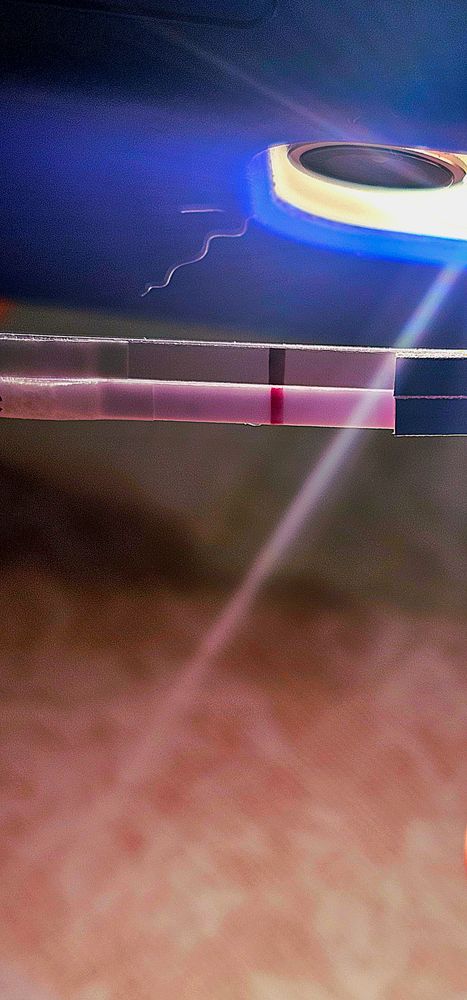

Делала ночью на 6 дпо. На двух леди чек увидела эти полосочки. Сейчас 9 дпо тесты чистые. Но я не сдаюсь,надеюсь)

Из признаков ничего нет,иногда тянет справа и покалывает,но ,конечно,это не показатель. Тестов накупила целую упаковку,так что до дня х есть чем заняться)